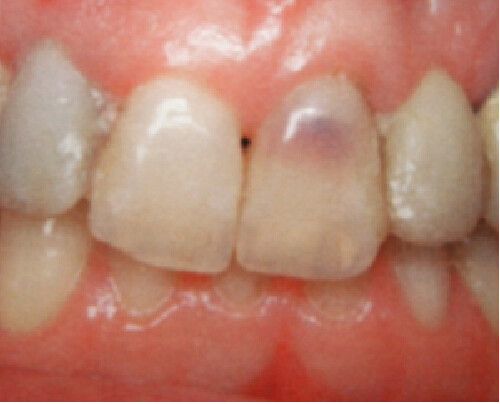

During an examination, dental hygienists may notice what seems to be a lightly discolored pink spot located at the cervical region of a tooth or even found in the crown showing through (figure 1). In both locations, this appearance, or “pink spot,” has to do with granulation tissue present underneath the enamel.

These pink spots are destructive and often insidious types of lesions that can occur either internally or externally on the tooth, resulting in significant loss of tooth structure. Both lesions have to do with a resorptive process that is occurring—often trauma-induced. When you discover these lesions, you can break down the resorptive processes based on their location: external or internal.

ECR can be differentiated from root caries due to its pink hue and tactile sensation. During the examination, you will find that the dentin surrounding an ECR lesion is usually hard, whereas decay/caries typically feels sticky. When a clinician performs probing around this type of lesion, it will typically bleed—often profusely—because of the highly vascular granulation tissue, a result of the resorptive process.

An internal resorption pink spot was historically referred to as the “pink tooth of Mummery,” named for the anatomist who described the condition. Like an ECR lesion, in this type of resorption, patients are typically asymptomatic, and the lesion is only noted either by its pink color that patients may notice prior to their visit or from routine radiographs.